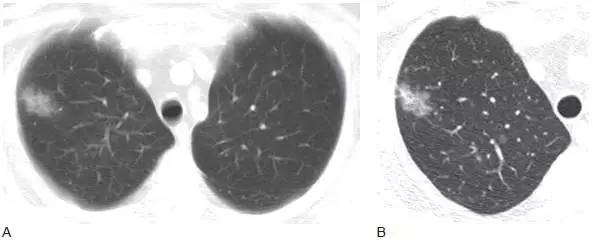

4、小细胞肺癌肺

小细胞肺癌常发生在主支气管或叶支气管,造成广泛的支气管周围侵犯,形成肺门增大或肺门旁肿块( 图10)。支气管腔内肿块较鳞癌少见,但大的肿块常压迫支气管( 图11) 引起肺不张。这种肿瘤常伴有显著的纵隔淋巴结增大( 图12),是引起上腔静脉阻塞综合征的常见原因。少于5%的病例表现为肺结节。

图10 小细胞肺癌

A. 胸片显示右肺门大肿块( 箭头);

B.CT 显示大肿块(M),中叶小叶间隔增厚引起的间质增厚提示肿瘤沿淋巴管播散